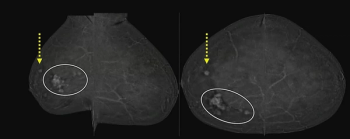

External validation testing revealed a deep learning combination of breast MRI, ultrasound and clinical factors had a 10 percent higher AUC for predicting axillary lymph node metastasis than sole use of MRI- or ultrasound-based deep learning models in patients with breast cancer.